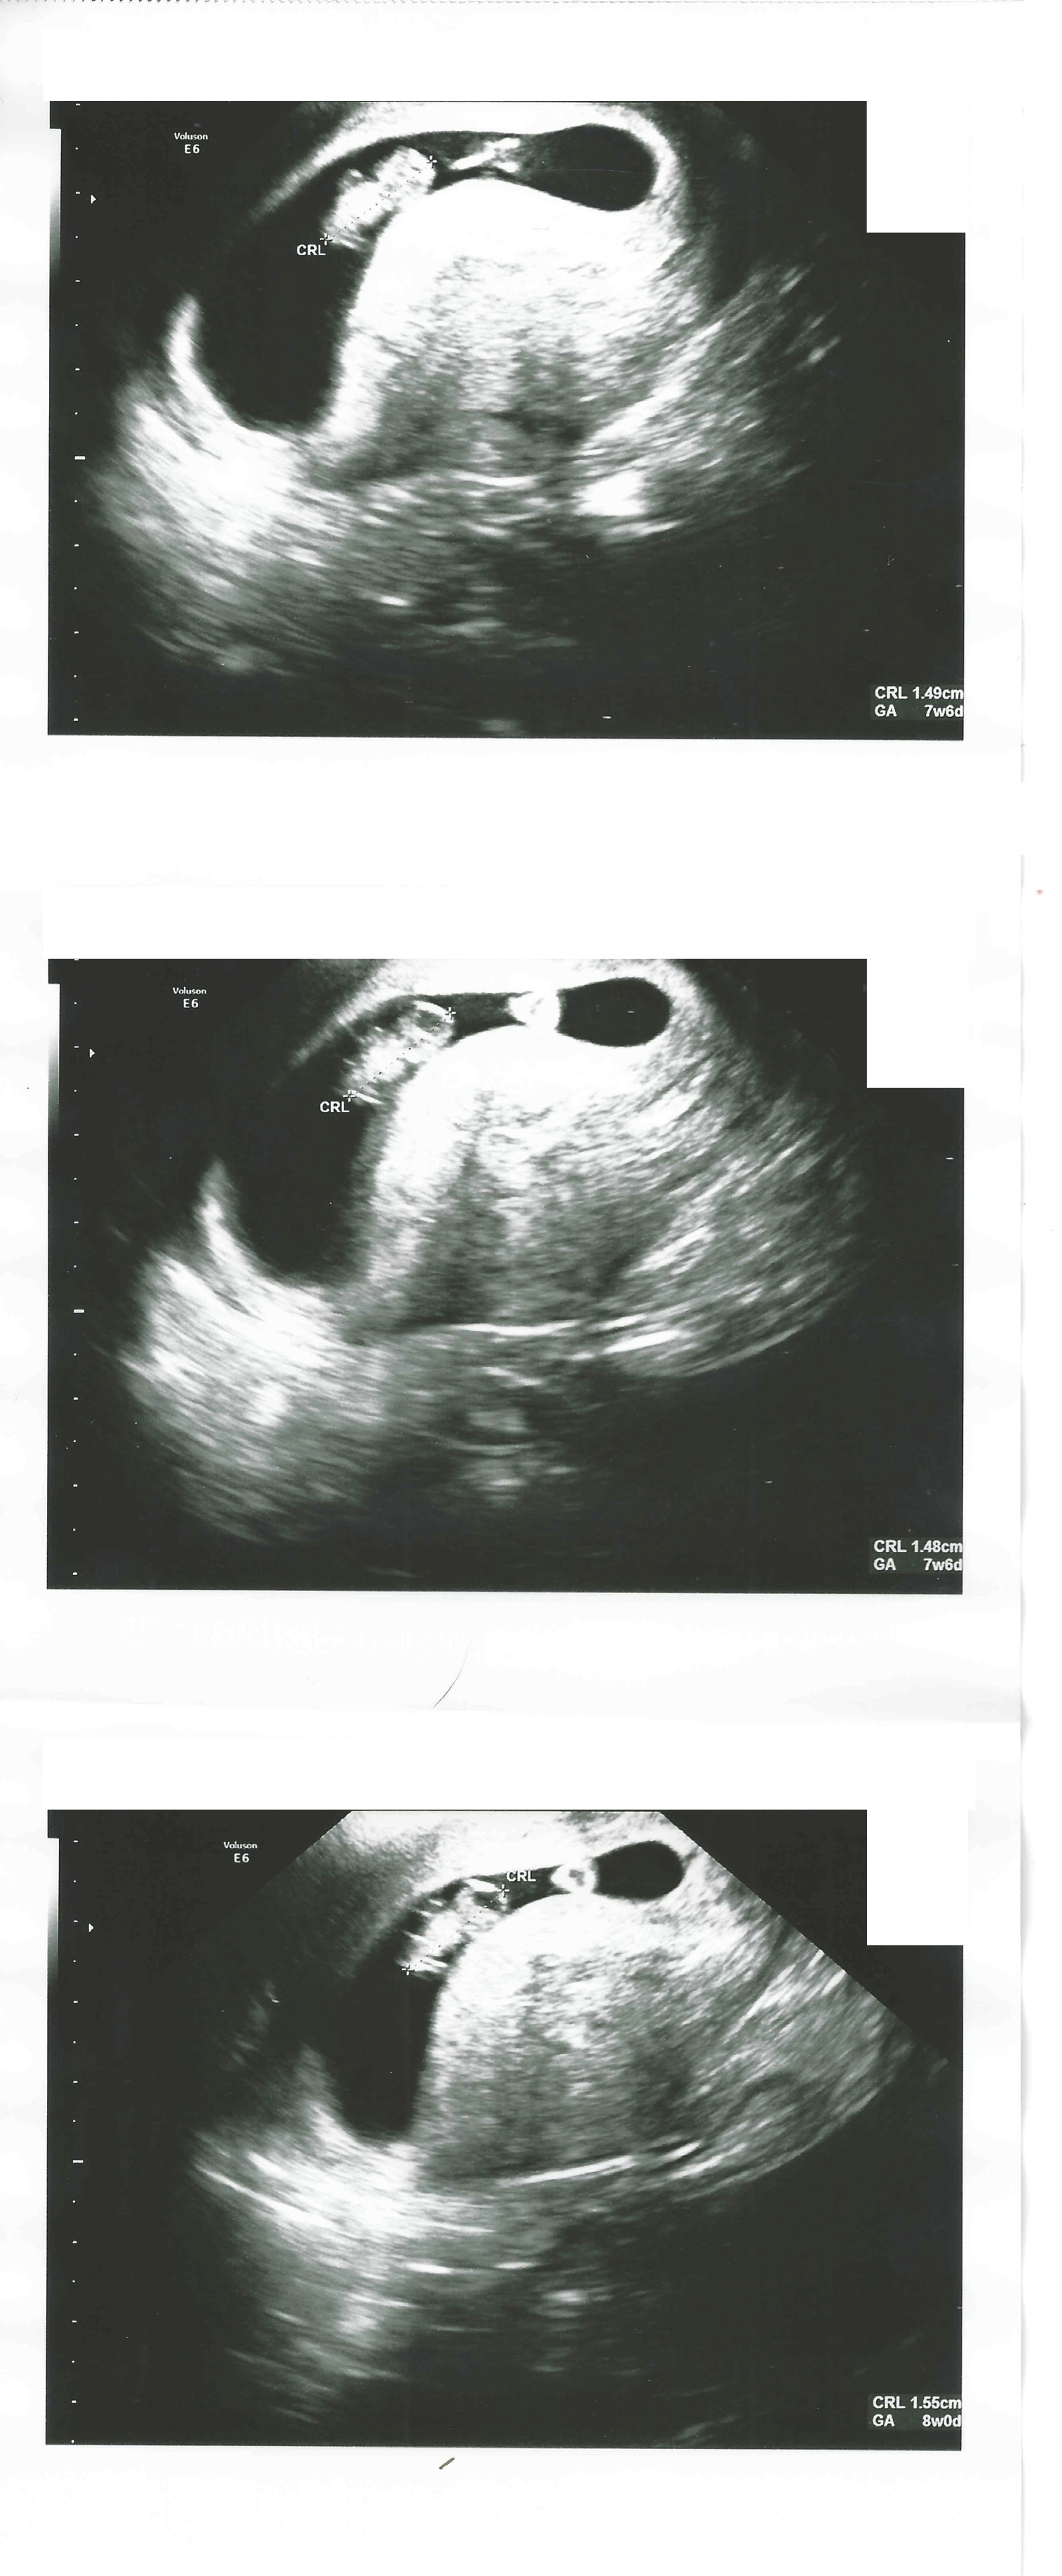

8 weken

Een echo na 8 weken.